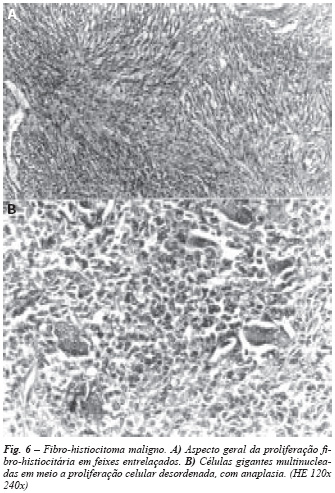

Fibro-histiocitoma maligno(12): quando intra-ósseo não apresenta aspectos clínico-radiográficos bem definidos.

Não tem localização preferencial e apresenta comportamento comum a outras neoplasias malignas. É a biópsia que permitirá diferenciá-lo de outros tumores. A neoplasia que a ele mais se assemelha é o fibrossarcoma, no qual estará presente apenas o componente fibroblástico com atipias, em meio a variável quantidade de fibras colágenas. No fibro-histiocitoma maligno o componente de células histiocitárias atípicas é acentuado, acompanhado de proliferação fibroblástica com variável quantidade de fibras colágenas. Com freqüência, os feixes de células neoplásicas assumem o clássico arranjo em turbilhões, chamado "aspecto estoriforme" (fig. 6). As células gigantes multinucleadas estão usualmente presentes e, às vezes, são numerosas, tornando-o por vezes indistinguível do tumor gigantocelular.